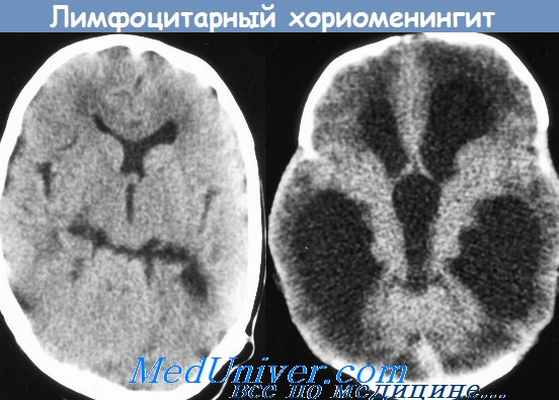

18. Лимфоцитарный хориоменингит Армстронга

Острый лимфоцитарный хориоменингит (синоним: острый серозный

менингит Армстронга, острый лимфоцитарный доброкачественный

менингит) — серозный менингит, вызываемый особым вирусом и

протекающий с преимущественным поражением сосудистых

сплетений мозга.

Патогенез. Вирус внедряется через слизистую оболочку верхних дыхательных путей и пищеварительного тракта, заносится в регионарные лимфатические узлы, где происходит его репликация. В результате гематогенной диссеминации возбудителя поражаются различные органы и ткани. Возникают воспалительные изменения в мозговых оболочках, эпендиме и сосудистых сплетениях желудочков мозга, что сопровождается гиперпродукцией цереброспинальной жидкости и развитием синдрома цереброспинальной гипертензии. При хроническом течении Х. л. происходит облитерация субарахноидального пространства, инфильтрация мозговых оболочек и вещества мозга.

Патологическая анатомия. Отмечаются выраженные отек, гиперемия и диффузная лимфоидная инфильтрация мягкой оболочки головного мозга, признаки повышенного внутричерепного давления (скопление цереброспинальной жидкости в субарахноидальном пространстве и желудочках), воспалительные изменения в сосудистых сплетениях желудочков мозга. Отек, гиперемия и лимфоцитарная инфильтрация наблюдаются также в легких и печени.

Серозный лимфоцитарный хориоменингит (болезнь Армстронга), как и энтеровирусные менингиты, протекает с поражением мягких мозговых оболочек и сосудистых сплетений головного мозга, характеризующимся морфологически лимфоцитарной инфильтрацией. Заболевание им связывают с увеличением численности и миграцией грызунов. Примерные сроки инкубации колеблются от 5-7 до 12 дней. Заболевание с развитием менингита начинается внезапно среди полного здоровья или МС появляется с началом второй волны лихорадки.

У больных отмечаются резкая головная боль, повторная рвота и общая слабость. Головная боль диффузная, мучительная или с локализацией в области лба и висков, сопровождается головокружением, болезненностью при движении глазных яблок, светобоязнью. МС имеет тенденцию к нарастанию в течение нескольких дней. Больные заторможены, плохо спят, аппетит снижен. Пульс часто отстает от температуры. В легких сухие хрипы. Могут быть увеличены печень и селезенка, отмечаются запоры. СМЖ прозрачная или опалесцирующая. Лимфоцитарный плеоцитоз (у 90%) от нескольких до 2 тыс. клеток; содержание белка повышено или нормальное. В крови чаще лейкопения, РОЭ нормальная или несколько ускорена. Заболевание продолжается от нескольких дней до 2 мес. СМЖ нормализуется позднее клинического выздоровления, плеоцитоз сохраняется в течение нескольких дней и даже месяцев. Течение заболевания сопровождается периодами обострения.